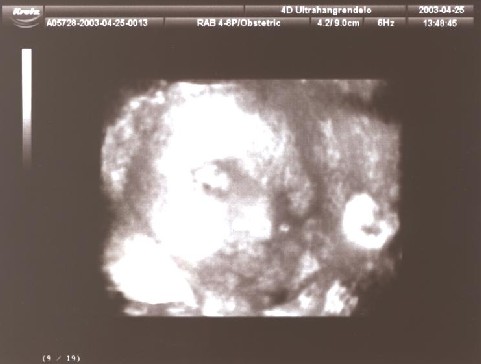

A két következő már háromdimenziós technikával készült. Ez valami újfajta nyavalya, még én sem értem teljesen. De azért integetek nektek egy jót!

Azt mondta a kedves doktor néni aki kezelte ezt a bonyolult berendezést, hogy apura fogok hasonlítani, talán a hörcsögpofim miatt. Hát én ezt nem tudom még, döntsd el inkább Te!